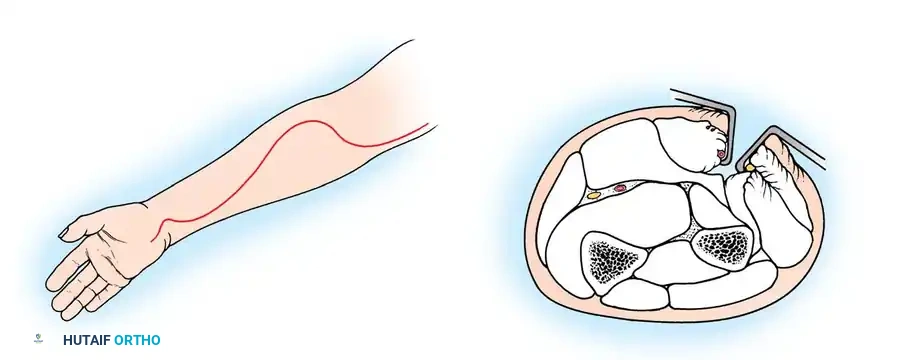

OPEN REDUCTION AND INTERNAL FIXATION (ORIF)

If closed and percutaneous methods fail to achieve <45 degrees of angulation, open reduction is mandated.

Timing: Surgery must be performed within 5 to 7 days of injury. Delayed surgical intervention drastically increases the risk of myositis ossificans and radioulnar synostosis.

Surgical Approach (Kocher Interval)

- Incision: A lateral Kocher incision is utilized, exploiting the internervous plane between the anconeus (radial nerve) and the extensor carpi ulnaris (posterior interosseous nerve).

- Exposure: The joint capsule is incised anterior to the lateral ulnar collateral ligament (LUCL) to prevent iatrogenic posterolateral rotatory instability (PLRI).

- Fixation: Internal fixation is strictly required; periosteal sutures alone are inadequate. Oblique pins across the fracture are preferred.

Surgical Warning: Avoid transcapitellar (transarticular) wires if possible. While technically easier to insert, they carry a high risk of intraarticular breakage and septic arthritis. Merchan and Fowles both reported significant hardware failure rates with transarticular pinning.

Anatomical Pitfall: During percutaneous reduction, the Kirschner wire must be introduced on the ulnar side of the radius. Introducing the wire laterally risks iatrogenic injury to the deep branch of the radial nerve (posterior interosseous nerve) as it traverses the arcade of Frohse.

Fig. 33-43 Radial neck fracture in relation to arcade of Frohse.